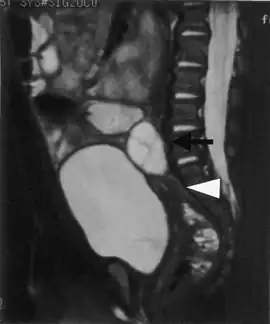

![]() | |

| AES results when the function of aromatase is impaired. The aromatase protein (pictured) is required for the biosynthesis of oestrogens like oestradiol in the human body. | |